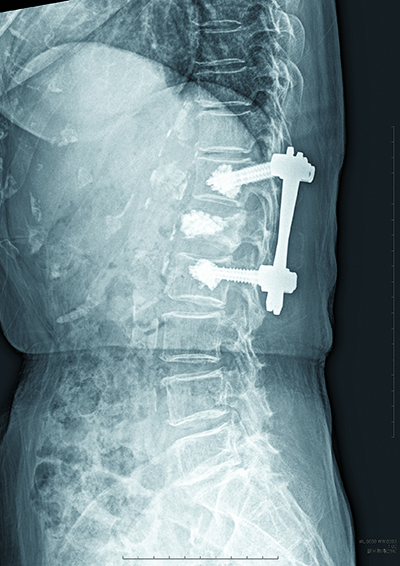

椎体固定術

脊椎のX線写真。黒く映っている下から5つ目の第1腰椎が骨折部位

つぶれた第1腰椎に顆粒状の人工骨を充填。その上下の椎体をスクリューとロッドで固定し、脊椎を安定させる